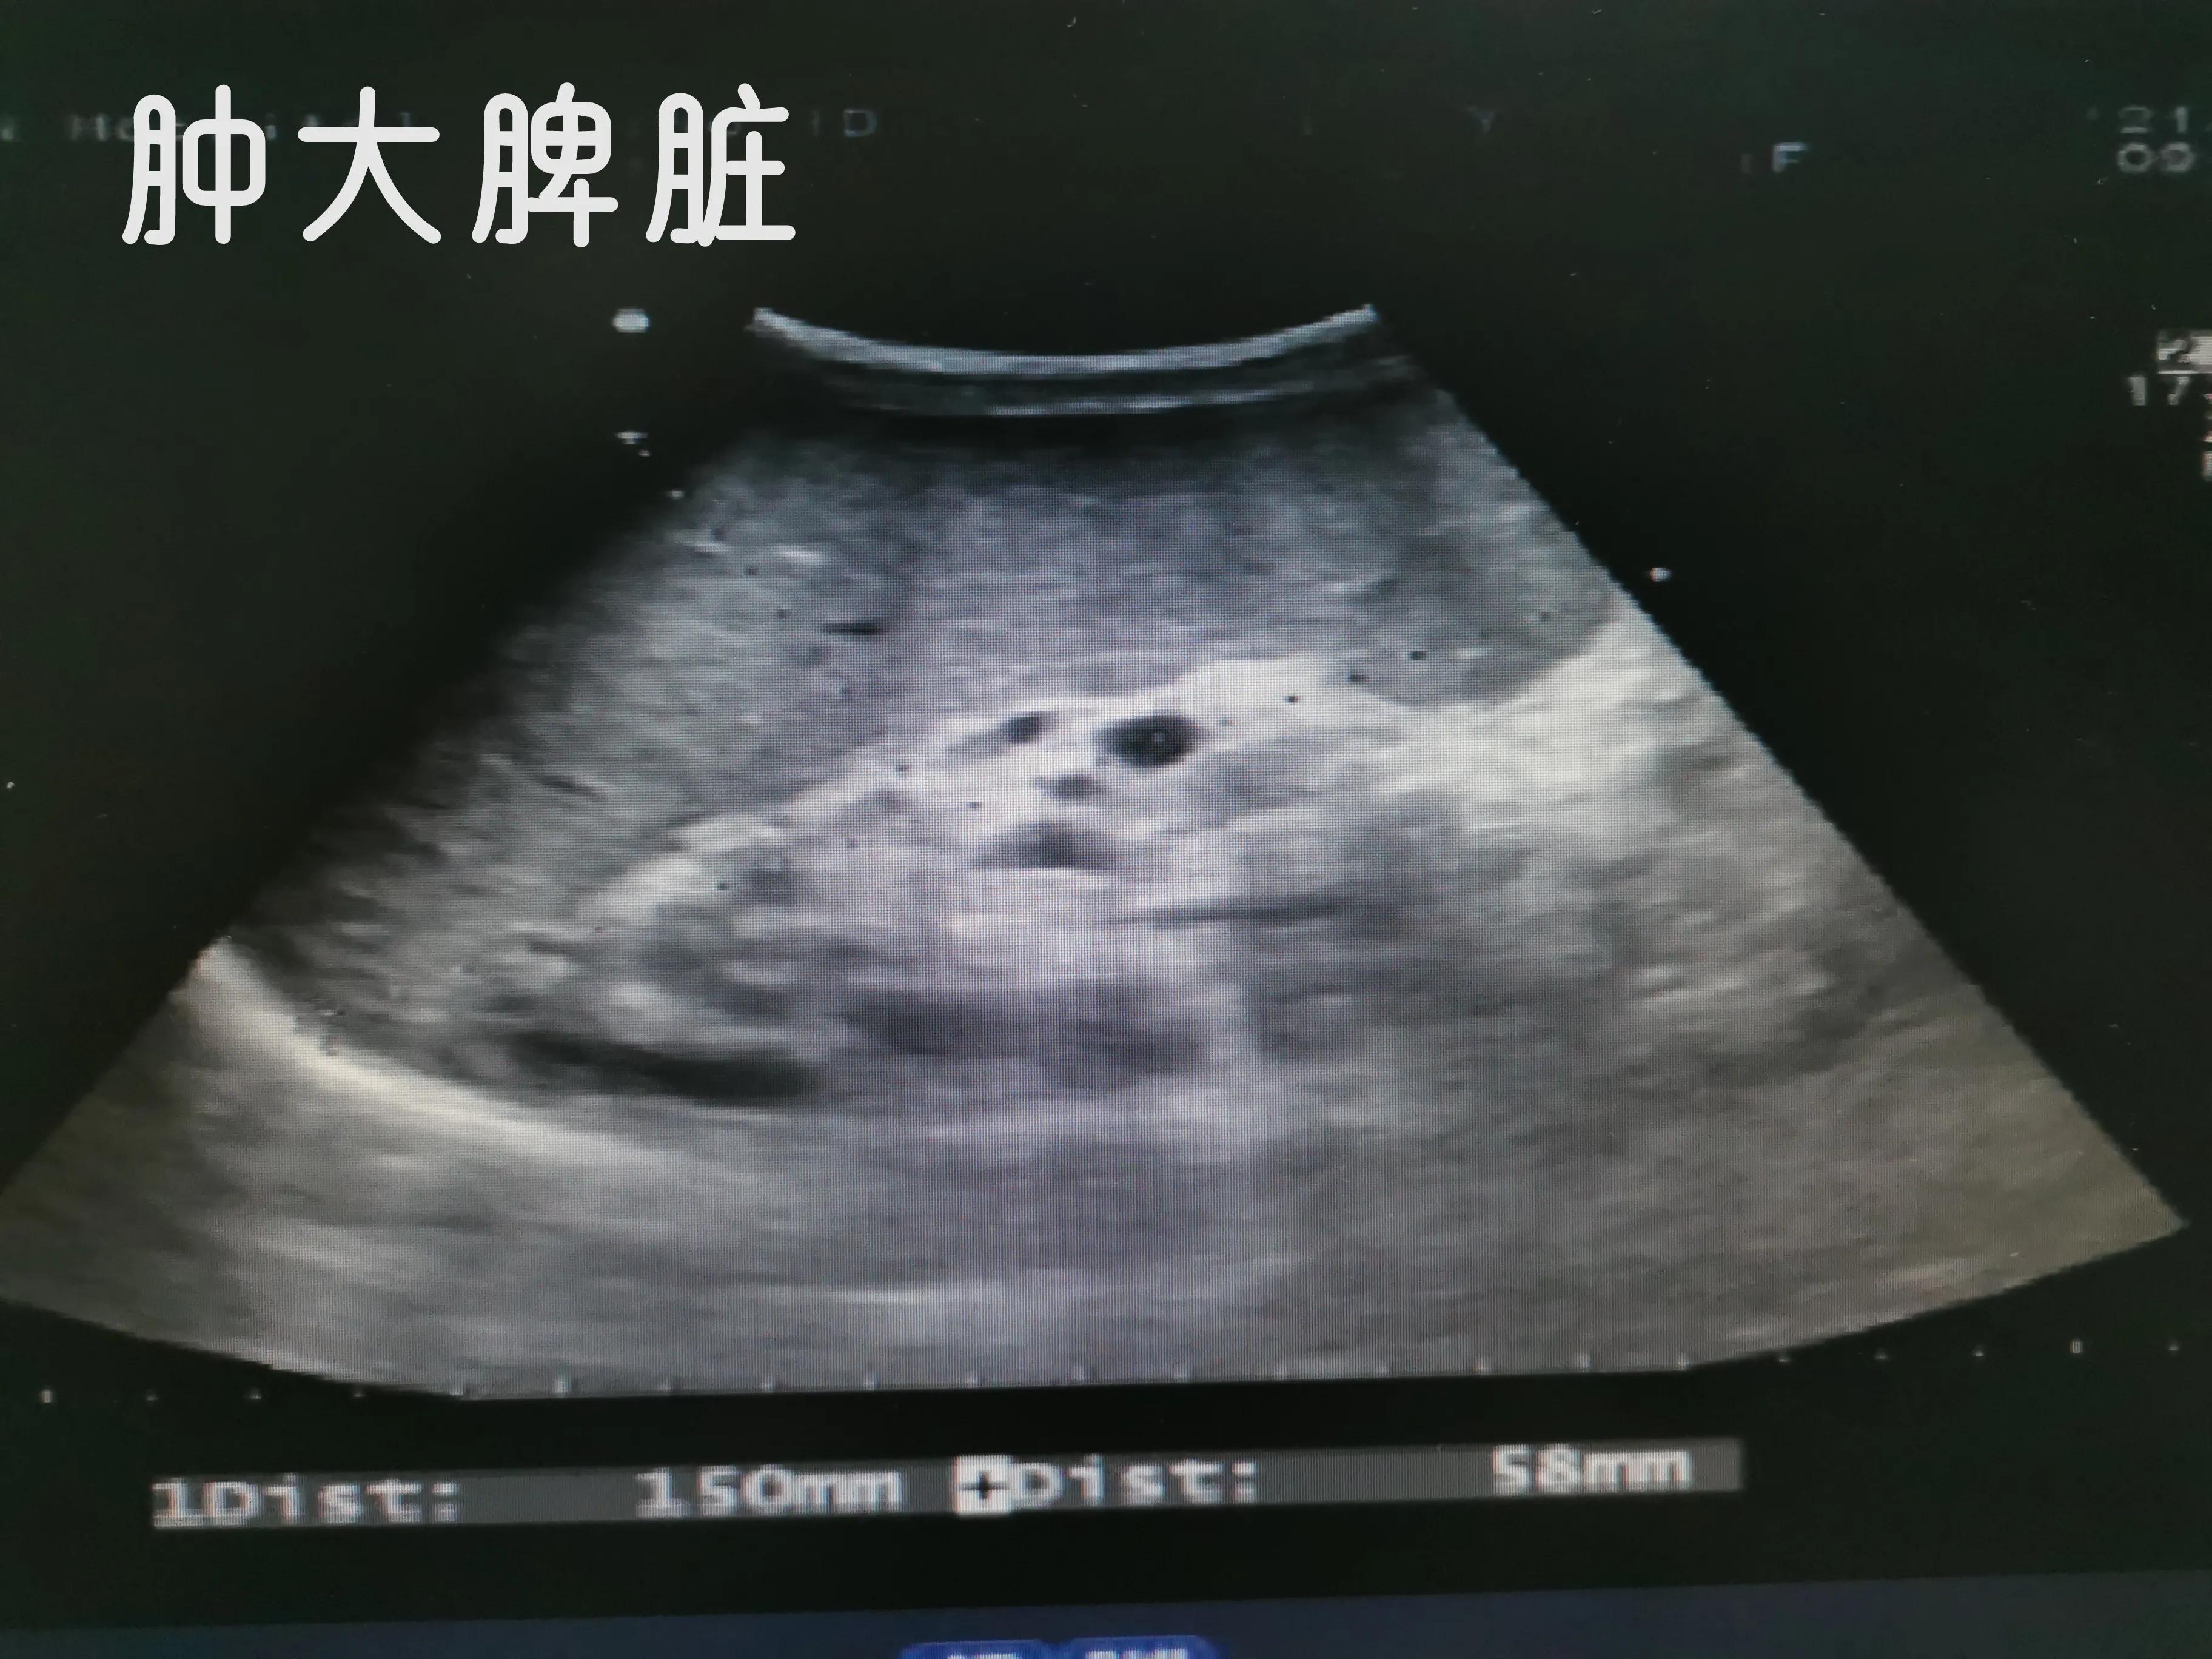

下面我们看看肝硬化失代偿期并肝癌病人肚子里面的情况

肝硬化病人,看起来大腹便便,里面是一肚子水